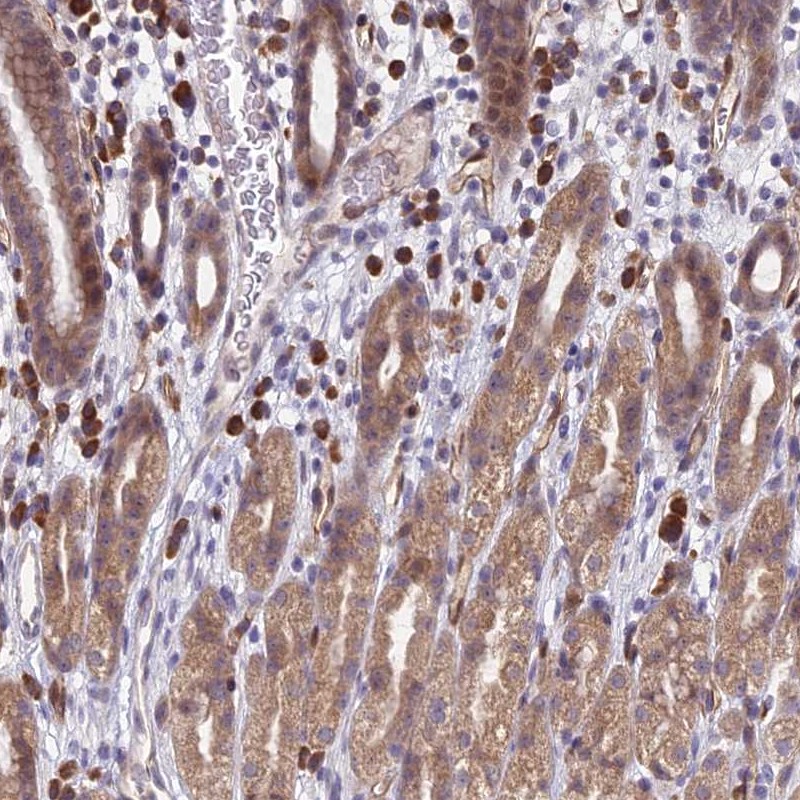

Immunohistochemical staining of human stomach, upper shows moderate cytoplasmic positivity in glandular cells.